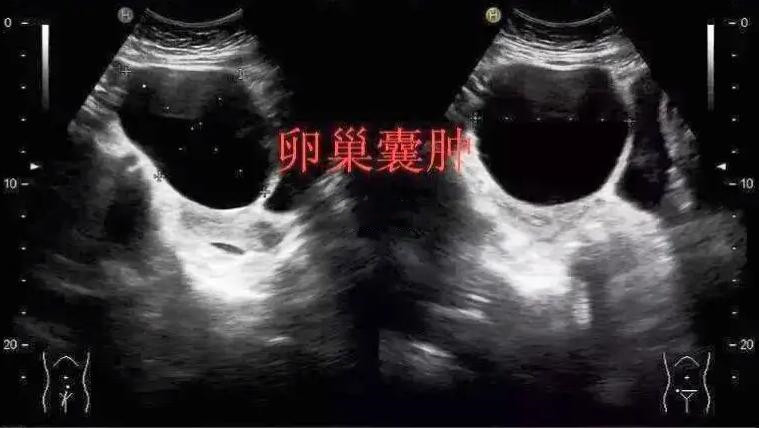

卵巢囊肿到底用不用手术?来看看这两位患者你就明白

报告单显示:右侧附件区见一大小约4.1*3.9*3.6 的囊性包块,边界清,没有其他症状,就是月经颜色暗、量少,舌质颜色暗,很明显就是瘀血阻滞的情况。